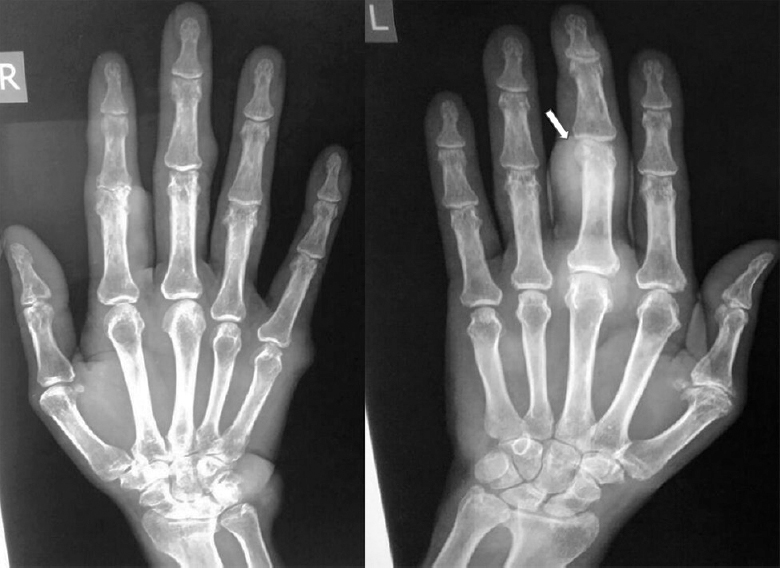

患者,男性,45岁,既往有糖尿病和高血压病史,因双手和右膝关节多发无痛性结节而就诊。检查结节不软、不活动、无红斑(图1)。双手的x线片显示无骨受累。图示左中指中指骨上皮下结节的软组织影(图2)、足部及左膝x线片示皮下结节。鉴别诊断包括转移、原发肿瘤和痛风,因为既往病史未发现任何关节炎的发作。

图2